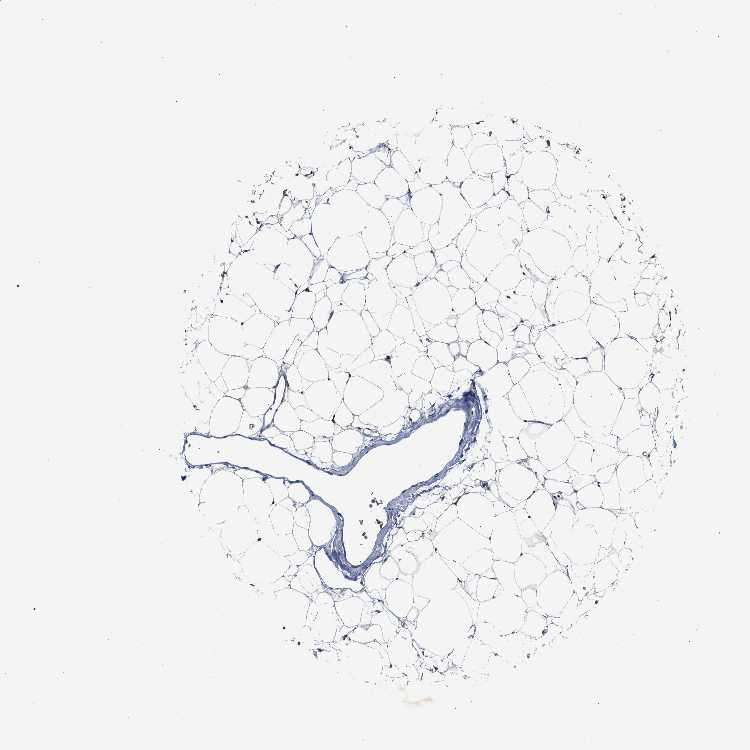

ADIPOSE TISSUE - Antibody stainingi

Antibody staining in the annotated cell types in the current human tissue is reported as not detected, low, medium, or high, based on conventional immunohistochemistry profiling in selected tissues. This score is based on the combination of the staining intensity and fraction of stained cells.

Each image is clickable and will lead to virtual microscopy that enables deeper exploration of all samples and also displays staining intensity scores, fraction scores and subcellular localization as well as patient and tissue information for each sample.

Antibody HPA019878Antibody HPA020096

Adipocytes MediumNot detected